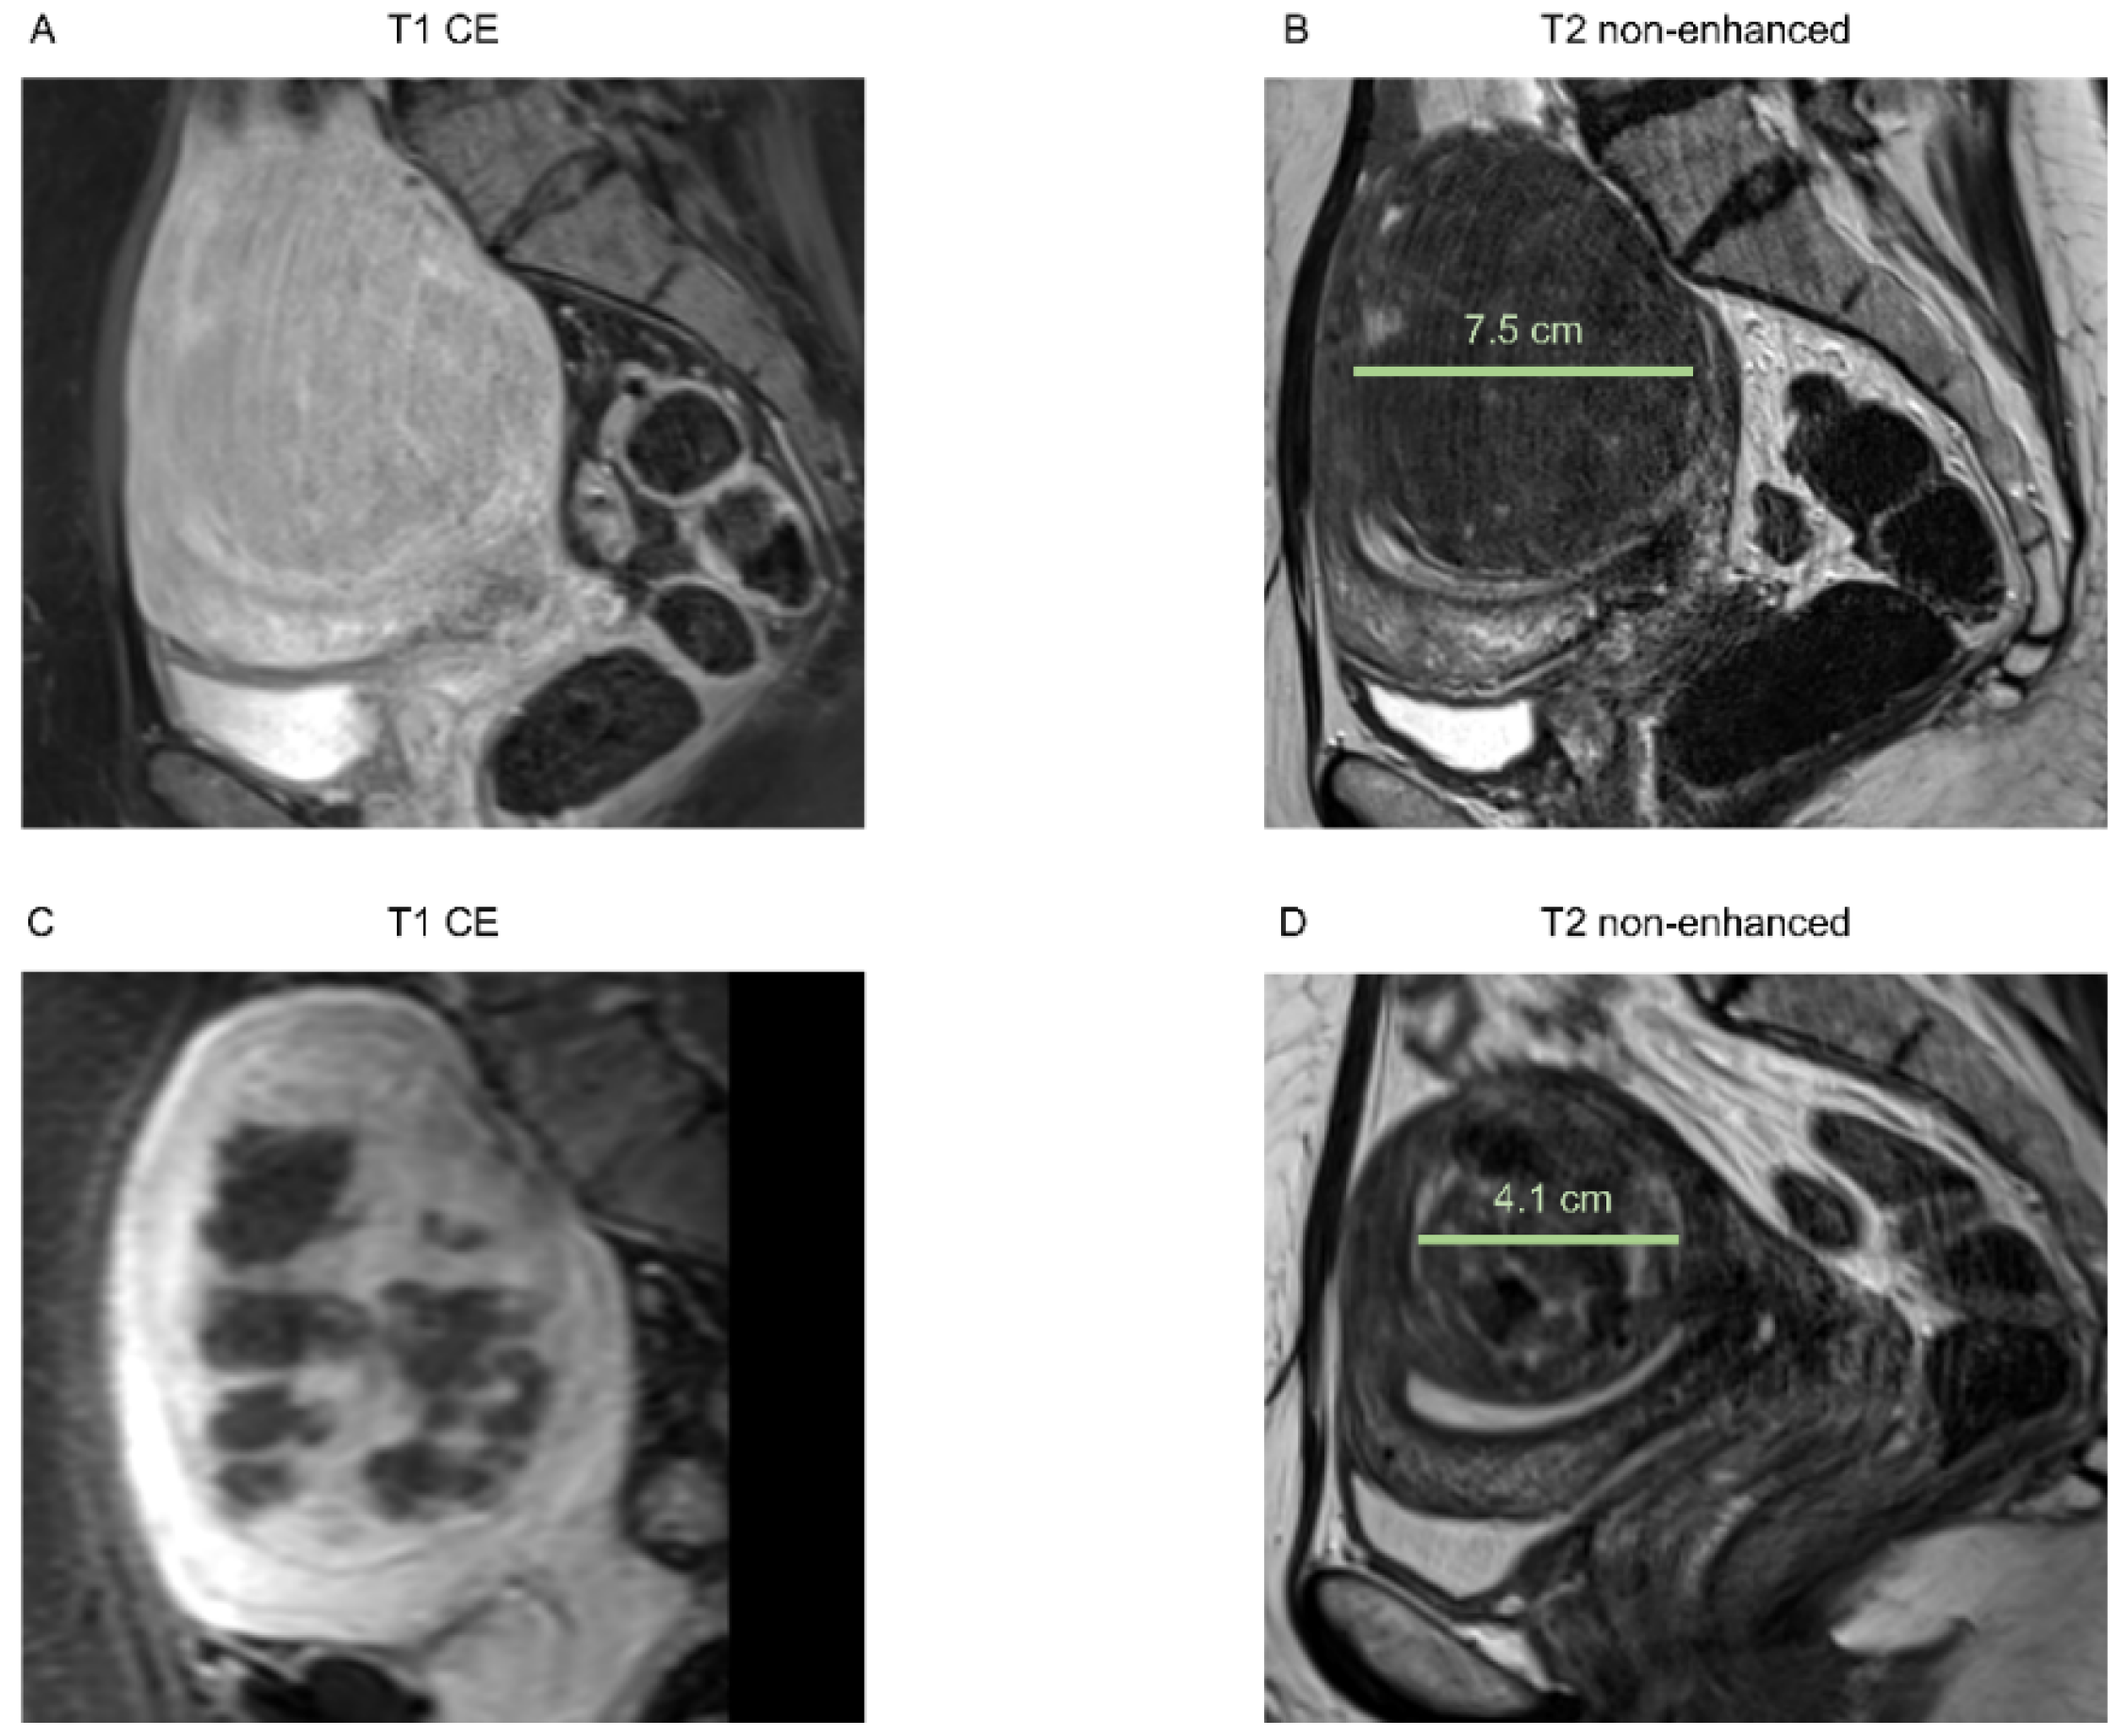

In Figure 1 and Figure 2, examples of an MRI of both groups are shown.

Figure 2. Images of a 39-year-old patient with multiple uterine fibroids in the anterior wall and posterior wall, Funaki grade 2. (A) Contrast-enhanced T1-weighted and (B) T2-weighted images 3 weeks before HIFU treatment of the fibroid in the anterior wall, sagittal reformation. Pre-interventional maximum diameter was 3.3 cm. A smaller subserous fibroid is depicted in the posterior wall (arrow), which could not be reached by HIFU due to bowel loops in the beam path. (C) Immediate post-interventional T1 contrast-enhanced image with a volumetric assessed NPV of 64%, sagittal reformation. (D) T2-weighted image 6 months after intervention with a maximum diameter of 2.0 cm, sagittal reformation.